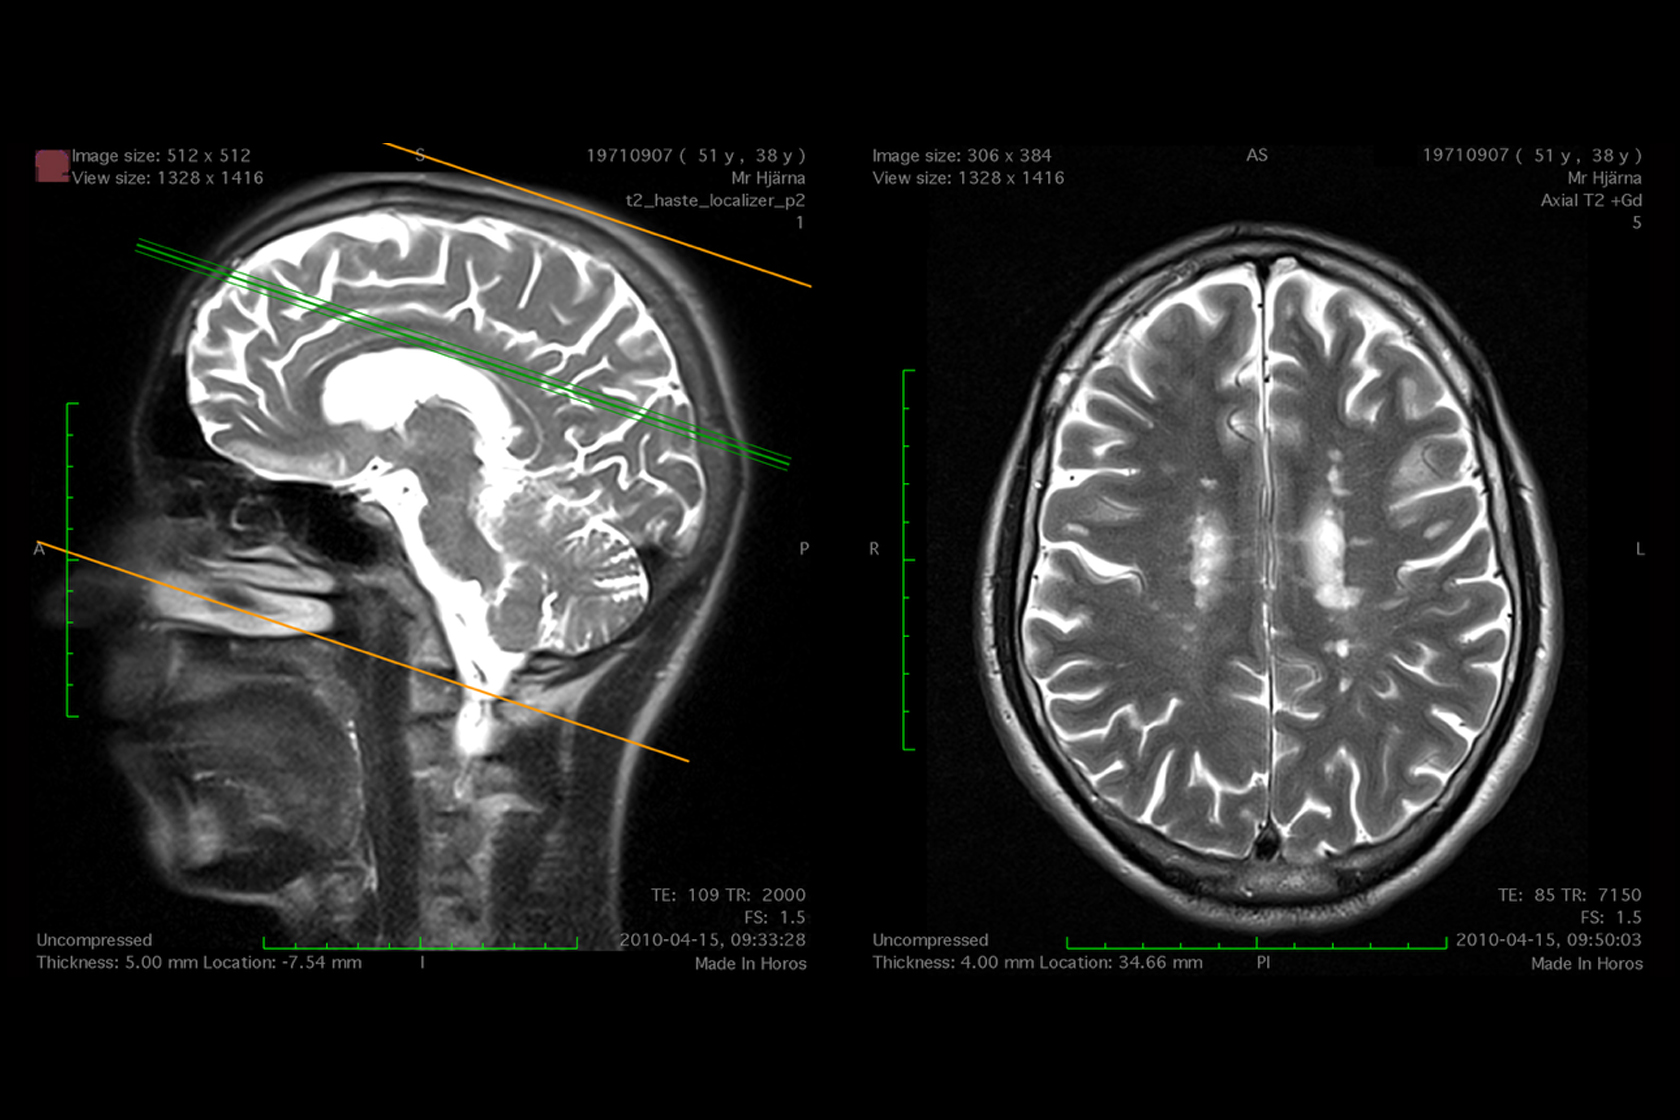

Black and white MRI scans of a human head in both profile and aerial view.

Goldin+Senneby, Spot Price: Tysabri (Biogen), 42.22mm, 2010/2023. KADIST Collection. Courtesy the artist

At the beginning of the new millennium, Jakob Senneby squinted at a grayscale image of his brain while a doctor traced a series of white blobs on the screen. His doctor told him that these figures, captured by an MRI scan, were “white spots”: signs of damage to the nervous system that are associated with multiple sclerosis. In the following years, Senneby—one half of the artist duo Goldin+Senneby—cycled through experimental and largely ineffectual treatments, tracking the progress of the disease with each scan, with each crop of “attacks” launched by his immune system. As he lost faith in the drugs, Senneby learned that the white spots have proven to be a source of immense, hidden value: a booming economy is based on visualizing, counting, and measuring the spots in the development of pharmaceuticals. The drugs have become more and more successful in treating the white spots in the image, but not in addressing the onset of permanent disability—the most critical consequence of the disease. Nevertheless, the value of the market for treatments has reached nearly $30 billion per year.

For Swallow Image, Goldin+Senneby will give a presentation on the evolution of “sick images”—depictions of illness that obscure the accounts of patients—and the lucrative market for MS drugs. The event picks up on Triple Canopy’s publication of two related works by Goldin+Senneby: "Spot Price," a blockchain-based artwork that links scans of Senneby’s diseased brain to the value of the drugs targeting such images; and “Regions of Interest,” an essay on living as a medical specimen and source of profit for drug companies.